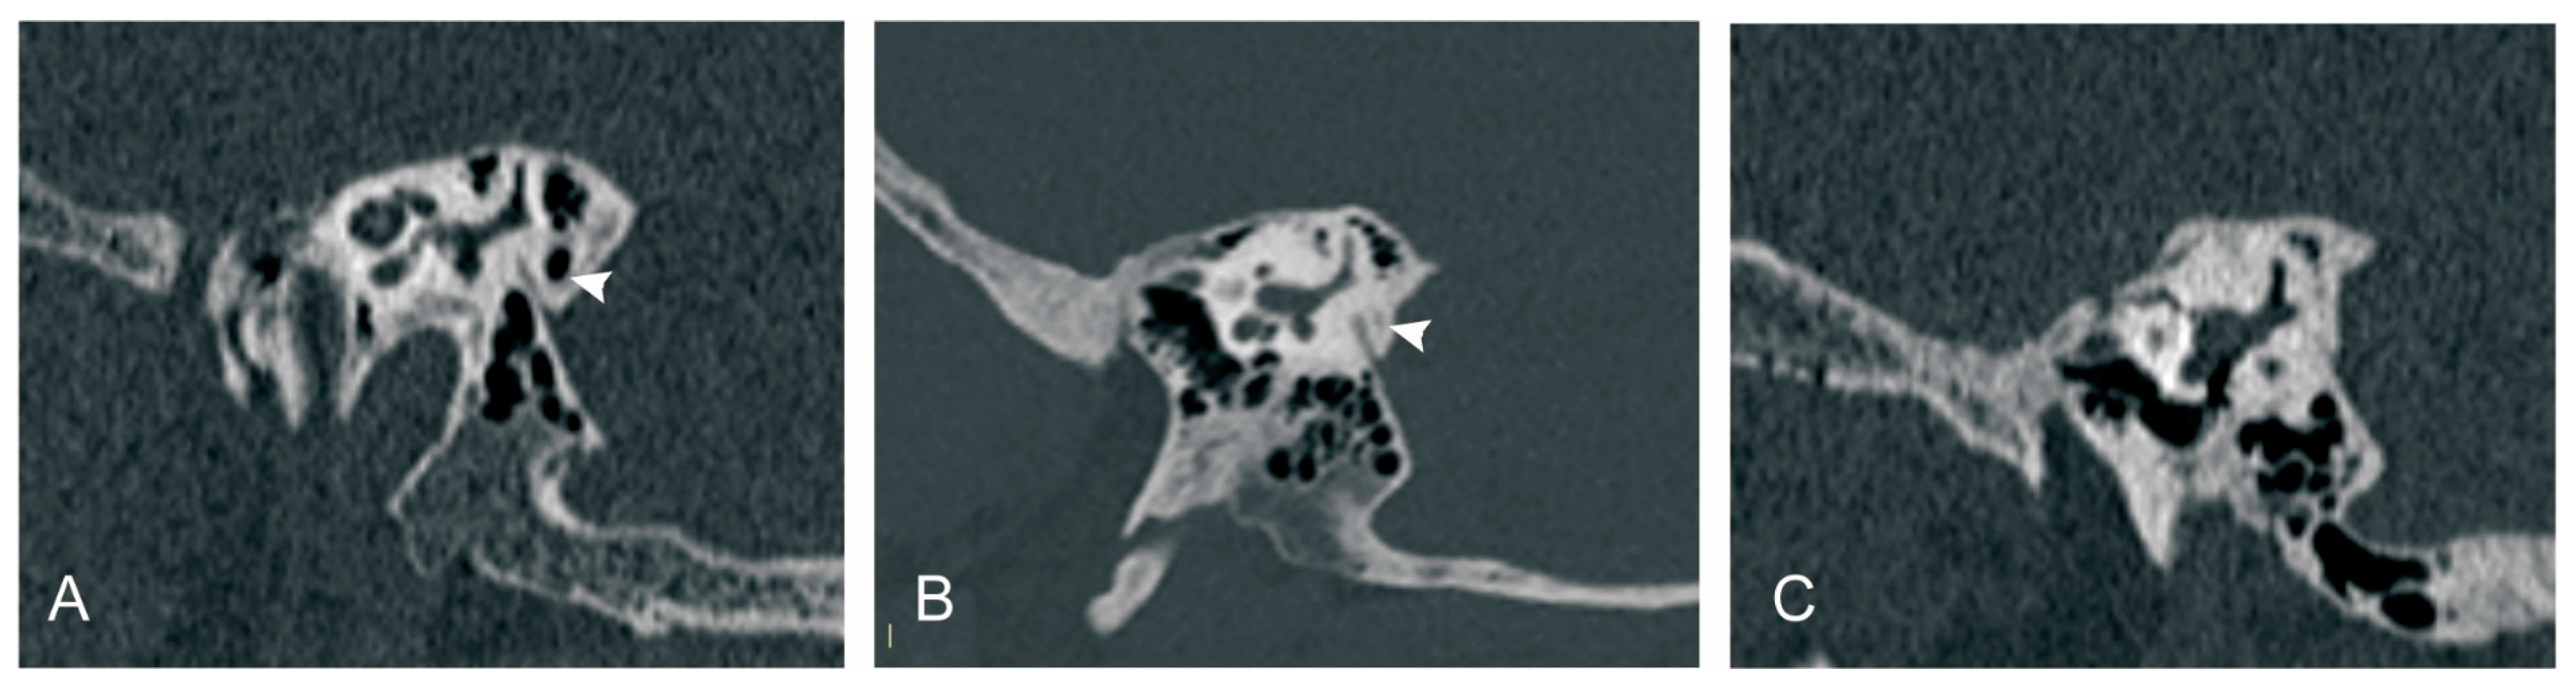

Peri-VA pneumatization was categorized according to published classification methods [22]: type 1: large-cell pneumatization in the vicinity of the VA; type 2: small-cell pneumatization in the vicinity of the VA; and type 3: absence of air cells (Figure 3).

Figure 3.

Peri-vestibular aqueduct (VA) pneumatization subtypes. (A) Large-cell pneumatization in the vicinity of the VA; (B) small-cell pneumatization in the vicinity of the VA; (C) absence of air cells. White arrowhead: peri-VA pneumatization.